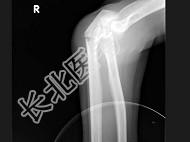

- 单项选择题女,55岁, 跌倒后右手痛,结合X线平片表现, 正确的诊断是 ( )

A、柯莱斯骨折

B、蒙泰贾骨折

C、加莱阿齐骨折

D、尺桡骨骨折

E、反柯莱阿齐骨折